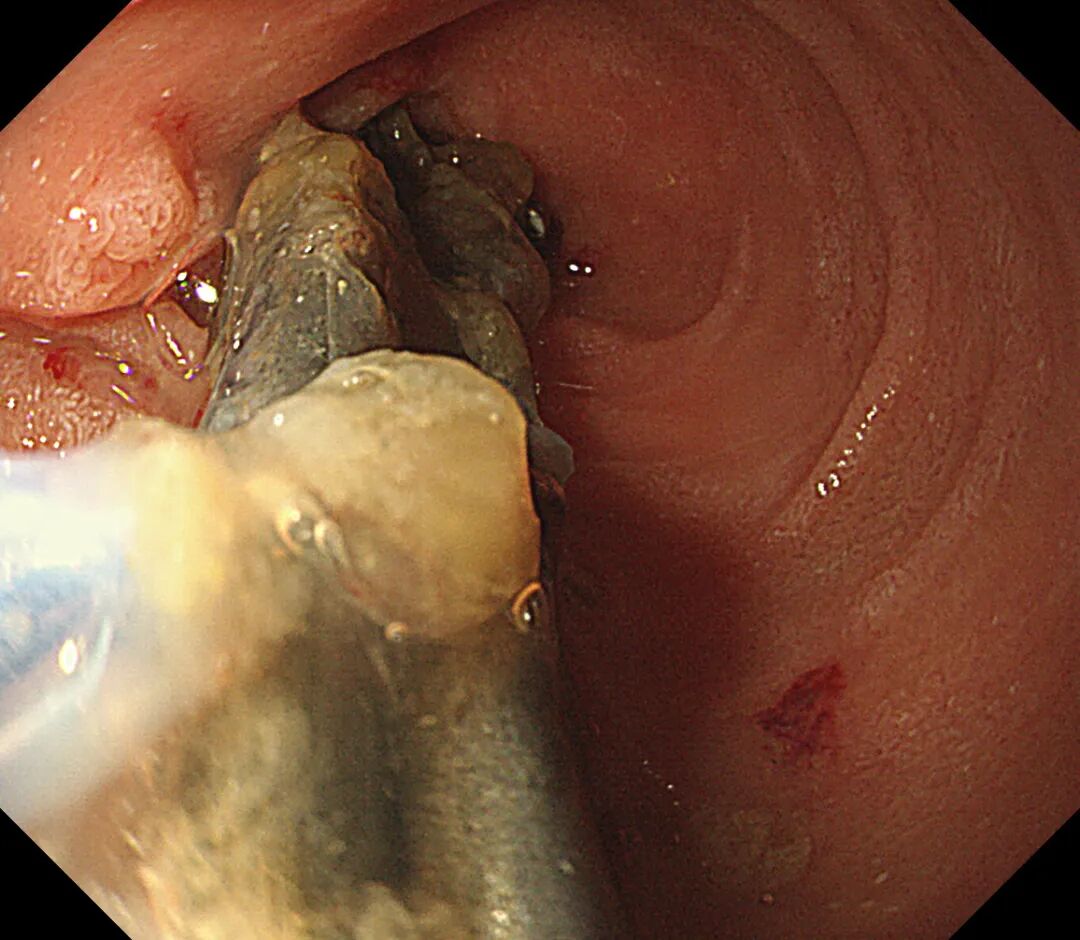

如何将风险降到最低,宜宾市中医医院立即开通绿色通道,多科协作,经讨论决定选择对娃娃损伤最小的全麻下经胃镜行消化道异物取出术。术中在胃镜下见4枚铁钉嵌顿于幽门口,随时有排入十二指肠的风险,立即予异物钳夹取,整个操作过程娴熟、流畅,成功将4枚铁钉完整取出。

4枚铁钉嵌顿于幽门口

铁钉成功取出后的幽门口